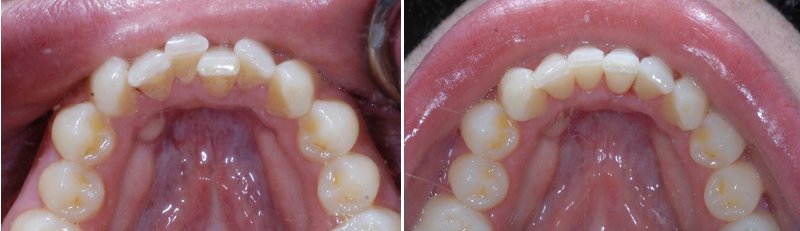

儿童牙齿拥挤矫正前后对比